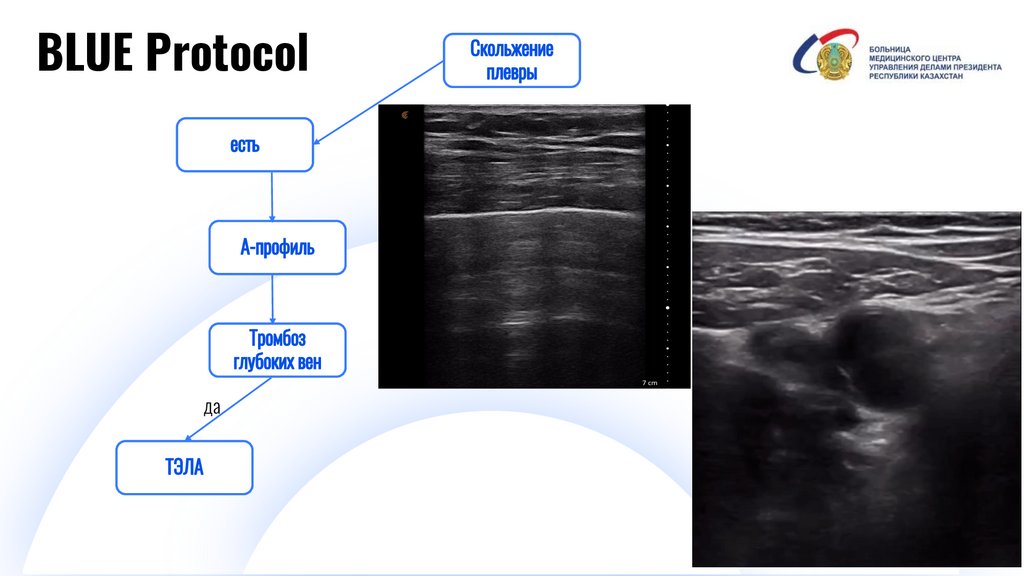

BLUE Protocol

да

Digital IT pitch-deck PowerPoint bundle

И

28